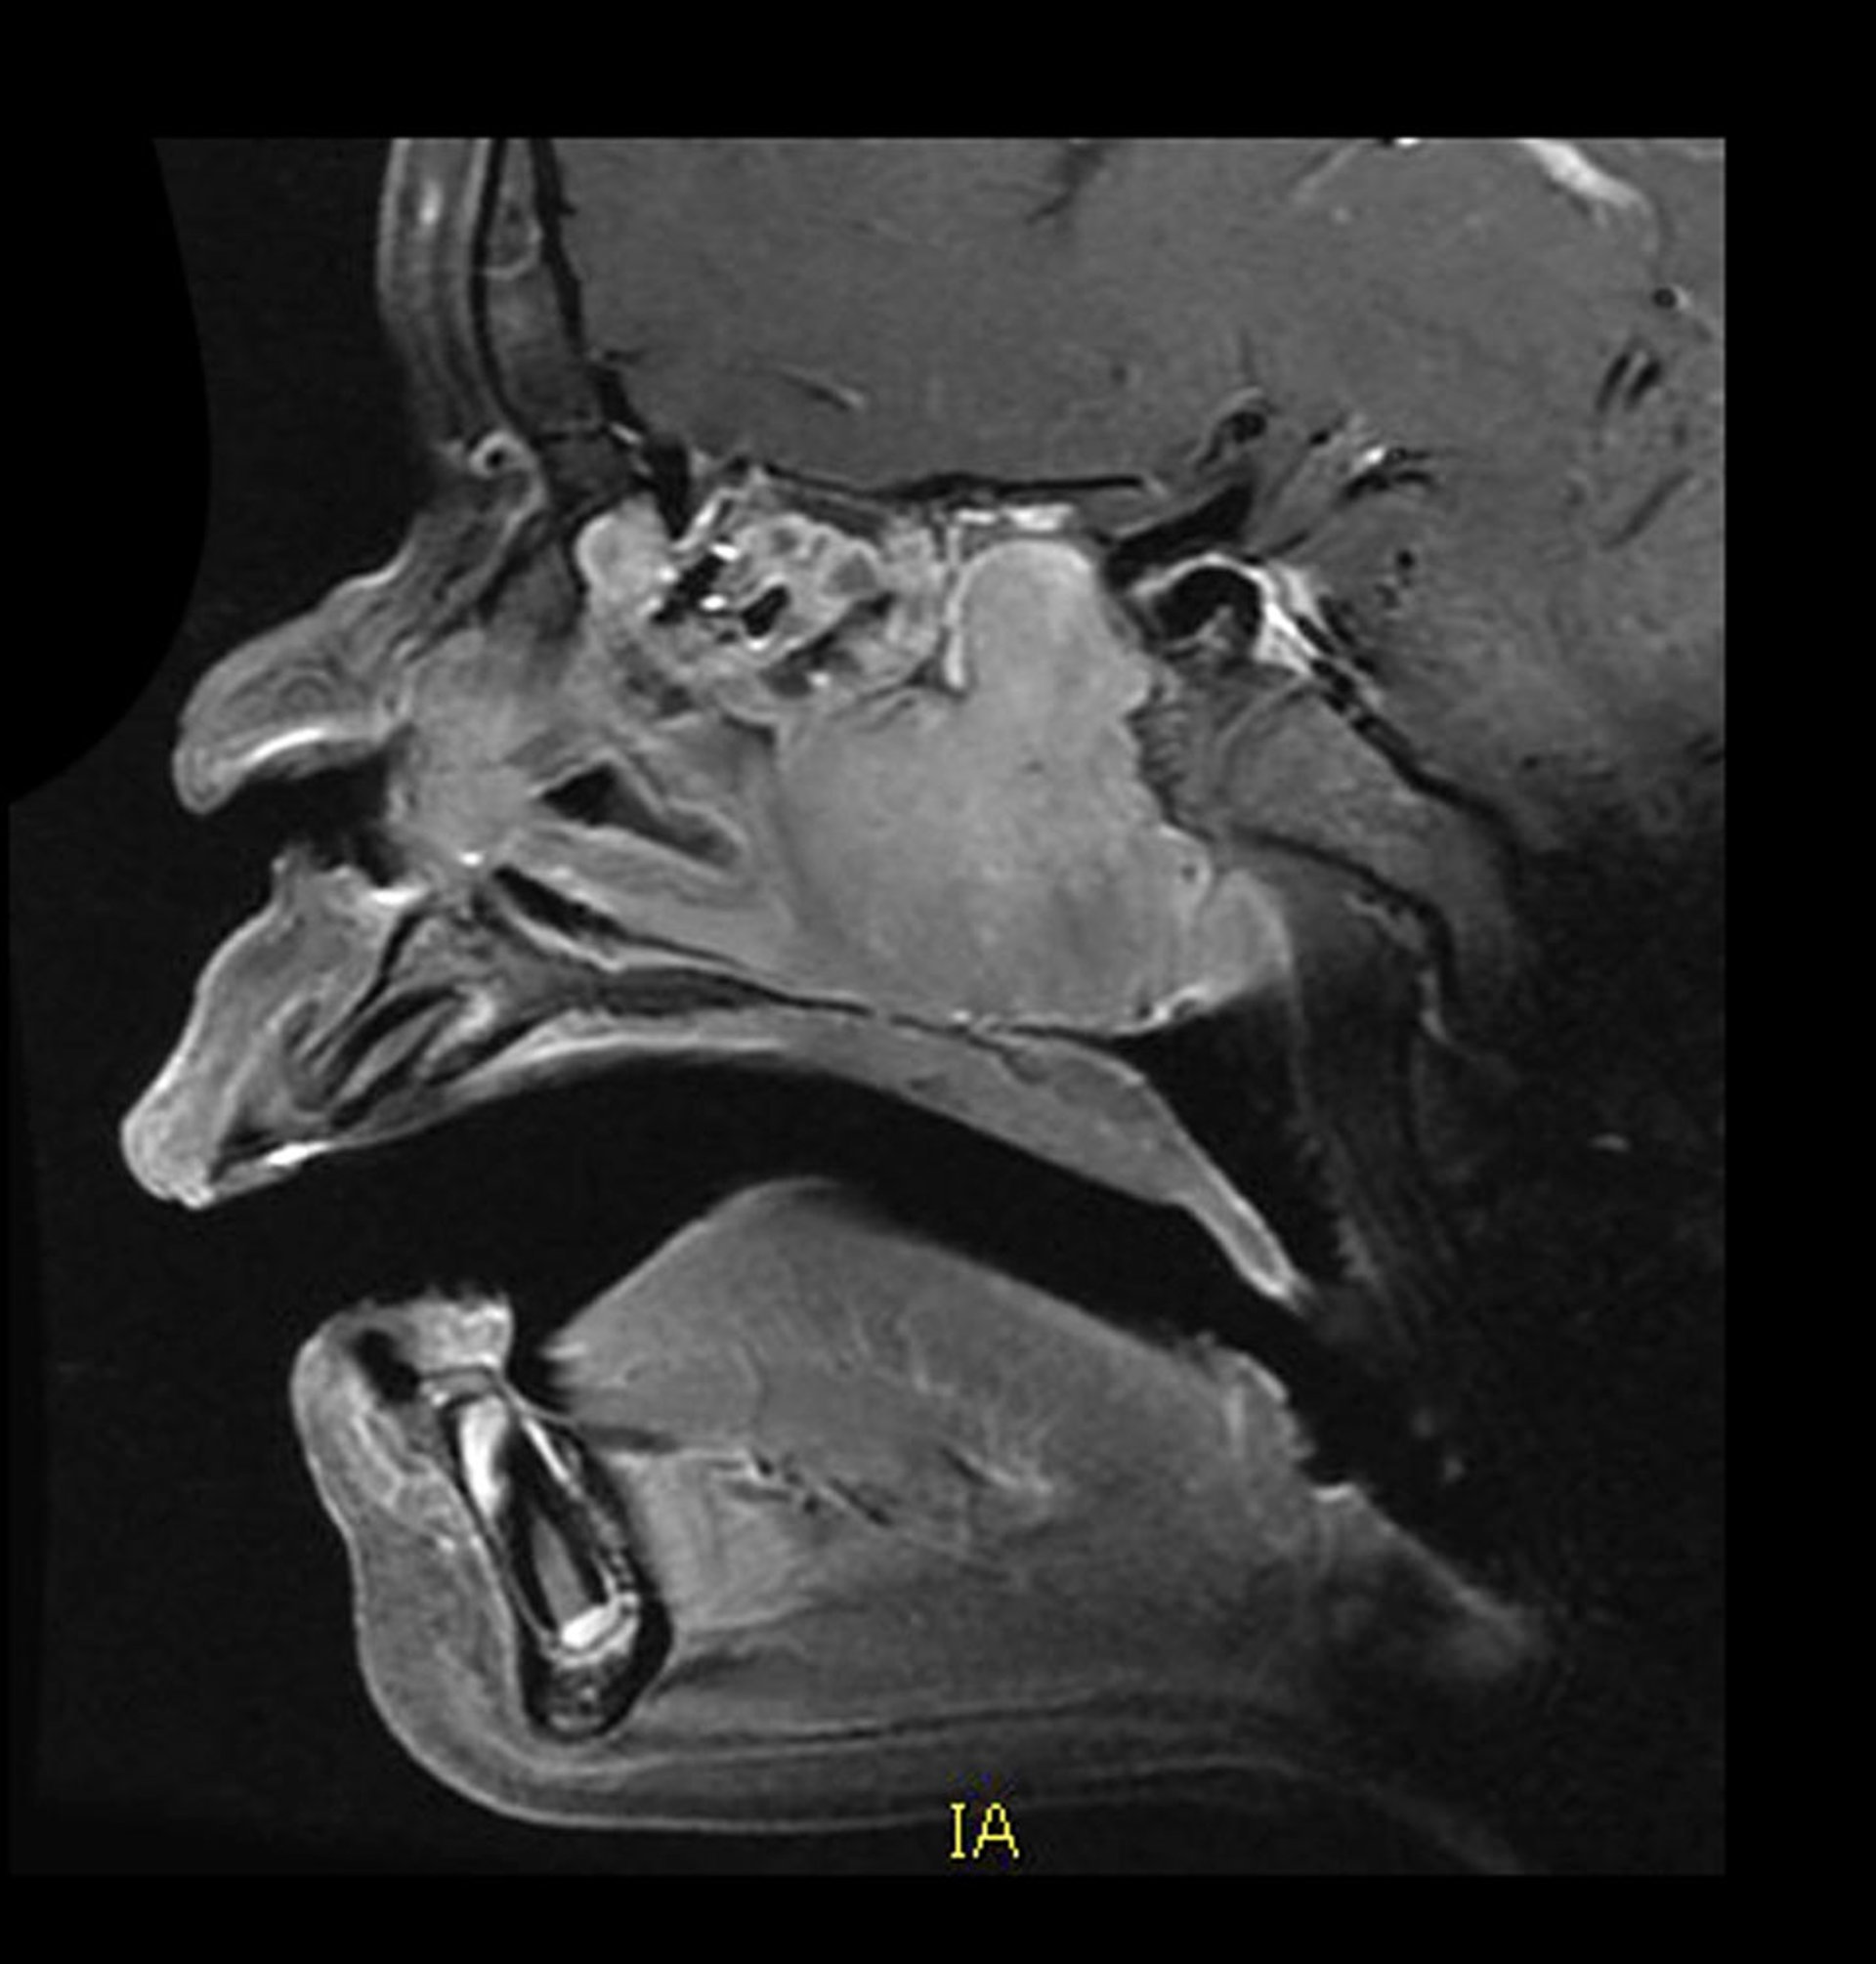

该矢状位增强MRI显示了典型部位和外观的血管性青少年鼻咽血管纤维瘤。后鼻腔可见一均匀强化的肿块,向后生长进入蝶窦。同时还伴有骨质破坏。

Living Art Enterprises/SCIENCE PHOTO LIBRARY